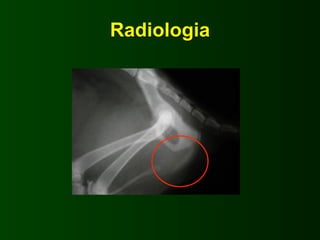

Radiologia

Uretrostomie • Très fréquente •Liée à une mauvaise alimentation ou à des désequilibres endocrinaux • L’ecographie est un excellent instrument